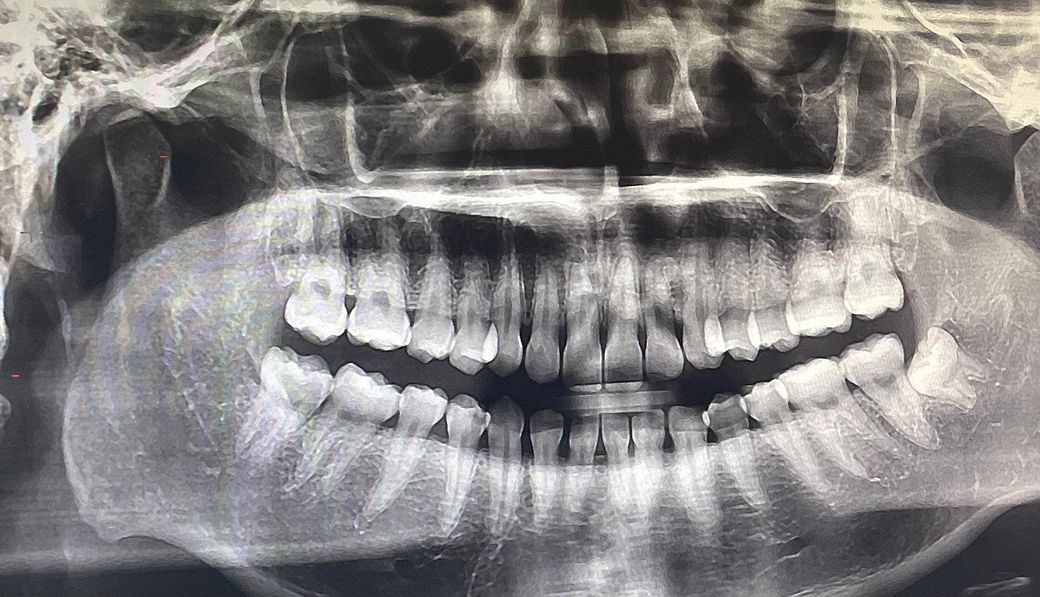

첫 번째 사진은 교정 시작 전에 찍은 엑스레이인데, 교정하고 뿌리가 더 짧아질 가능성이 있나요?

• 1번 째 사진

방사선 사진 상에서 치근 길이 엄청 짧거나 이상있어 보이지는 않으며 구내 사진 상에서도 큰 이상은 없어보입니다. 교정 치료 중에는 치아 이동에 따른 치근 흡수가 발생할 수 있으며 교장 합병증 중 하나입니다.

지금 첨부 주신 사진상에서는 큰 이상은 없어보입니다. 너무 걱정하지는 않으셔도 될 것 같으며 자세한 것들은 사진 자료가 있는 교정 치과에서 꼭 이야기 나눠보시기를 바랍니다.